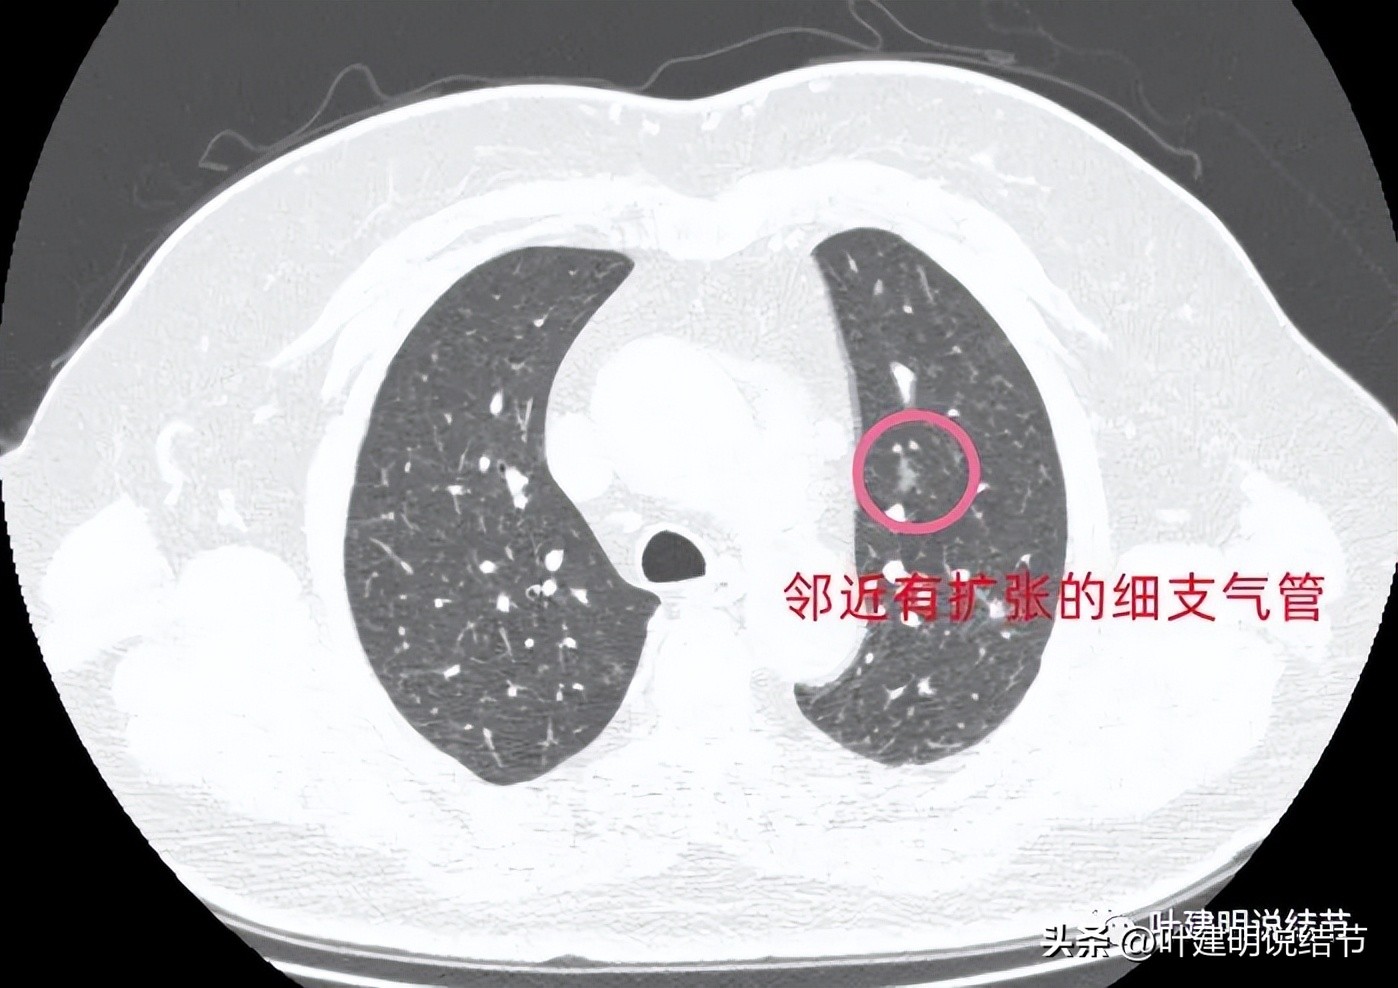

病灶5:左上叶磨玻璃影,斑片状,连续层面看邻近有扩张的细支气管。病灶轮廓较清,瘤肺边界似乎较为清楚